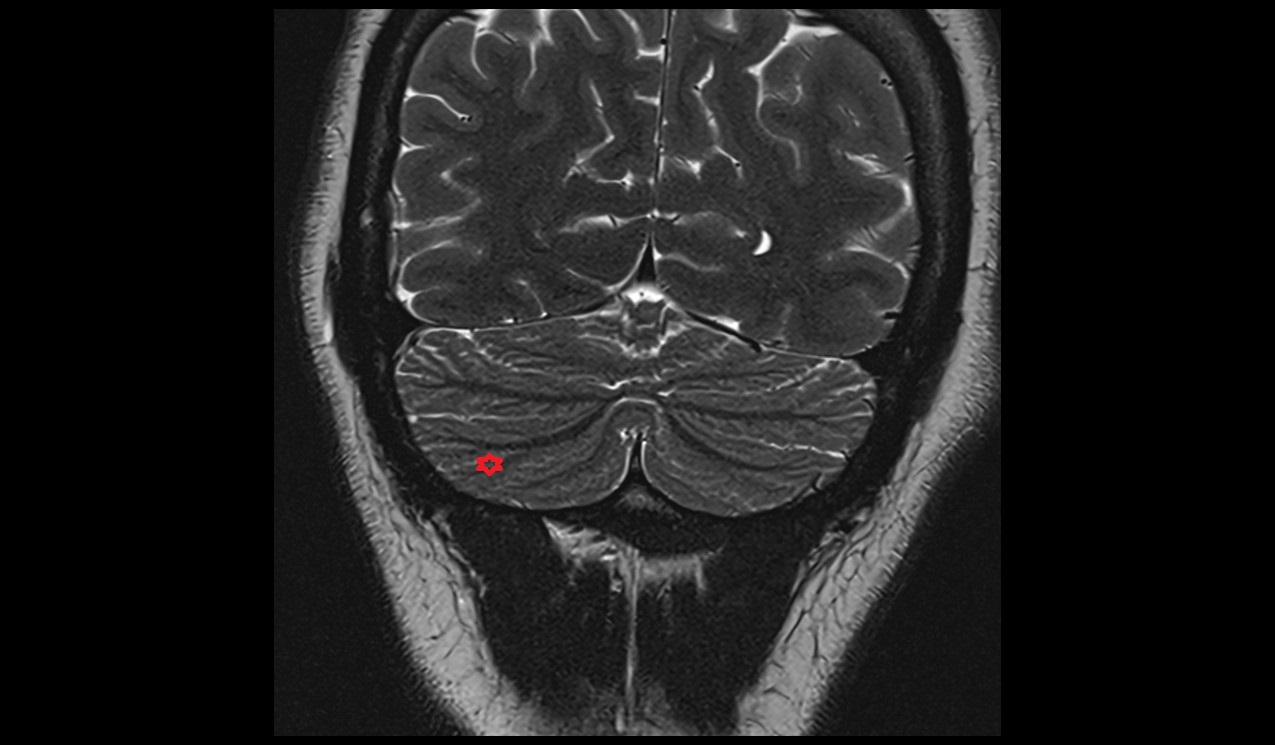

- Cerebellum

- Crus I of ansiform lobule of cerebellum

- Crus II of ansiform lobule of cerebellum

- Paramedian lobule (HVII) of cerebellum

- Simple lobule (HVI) of cerebellum